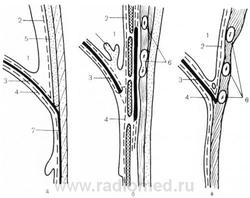

а — медиальный сагиттальный срез; б — парамедиальный сагиттальный срез через переднюю щель; в — через место прикрепления I ребра. 1 — сердце; 2 — плевра; 3 — диафрагма; 4 — париетальная брюшина; 5 — грудина; 6 — ребра; 7 — белая линия живота.

а — ретроманубриальный доступ Кондорелли — Казанского; б — парастернальный доступ Розенштрауха — Эндера; в — ретроксифоидальный доступ Бальма — Тевене в модификации Кривенко.

Образование абдоминомедиастинальной грыжи

1 — сердце; 2 — легочная ткань; 3 — диафрагма; 4 — абдоминомедиастинальная грыжа; 5 плевральная складка; 6 — грудина; 7 — печень; 8 — белая линия живота; 9 — брюшина (Таgliacozzo S., 1964).